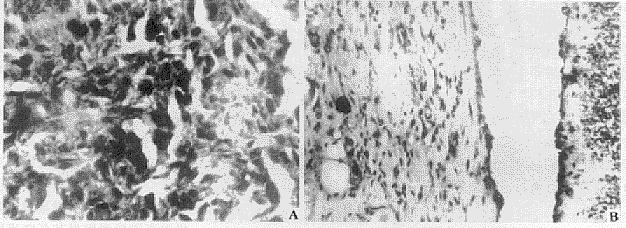

伤后7 d,各组创面内均出现多量肉芽组织。其中以未照射组肉芽组织层最厚,成纤维细胞和新生毛细血管含量最为丰富(图3A),新生表皮细胞也已覆盖大部分创面;而伤后即刻照射组肉芽组织层明显较对照组薄,其中新生血管数量亦较少,表面常有出血(图3B);伤前2 d照射组和伤后3 d照射组肉芽组织厚度介于上述两组之间,伤后7 d照射组与未照射组相近。免疫组化和原位杂交结果显示:未照射组肉芽组织中Ⅲ型胶原蛋白呈强阳性(+++)(图4A),其成纤维细胞内Ⅰ、Ⅲ型胶原mRNA亦均显示较强阳性(+++);而伤后即刻照射组创面组织内Ⅲ型胶原蛋白阳性程度较弱(+)(图4B),其成纤维细胞内Ⅰ、Ⅲ型胶原mRNA亦均呈弱阳性(+);伤前2 d和伤后3 d照射组胶原基因转录及胶原蛋白表达强度介于上述两组之间,伤后7 d照射组与未照射组相近。

图4 致伤后不同时间创面的变化

伤后7天,未照射组肉芽组织中Ⅲ型胶原蛋白强阳性(A);伤后即刻照射组肉芽组织

中Ⅲ型胶原蛋白阳性程度较弱(B)。免疫组化染色 ×300